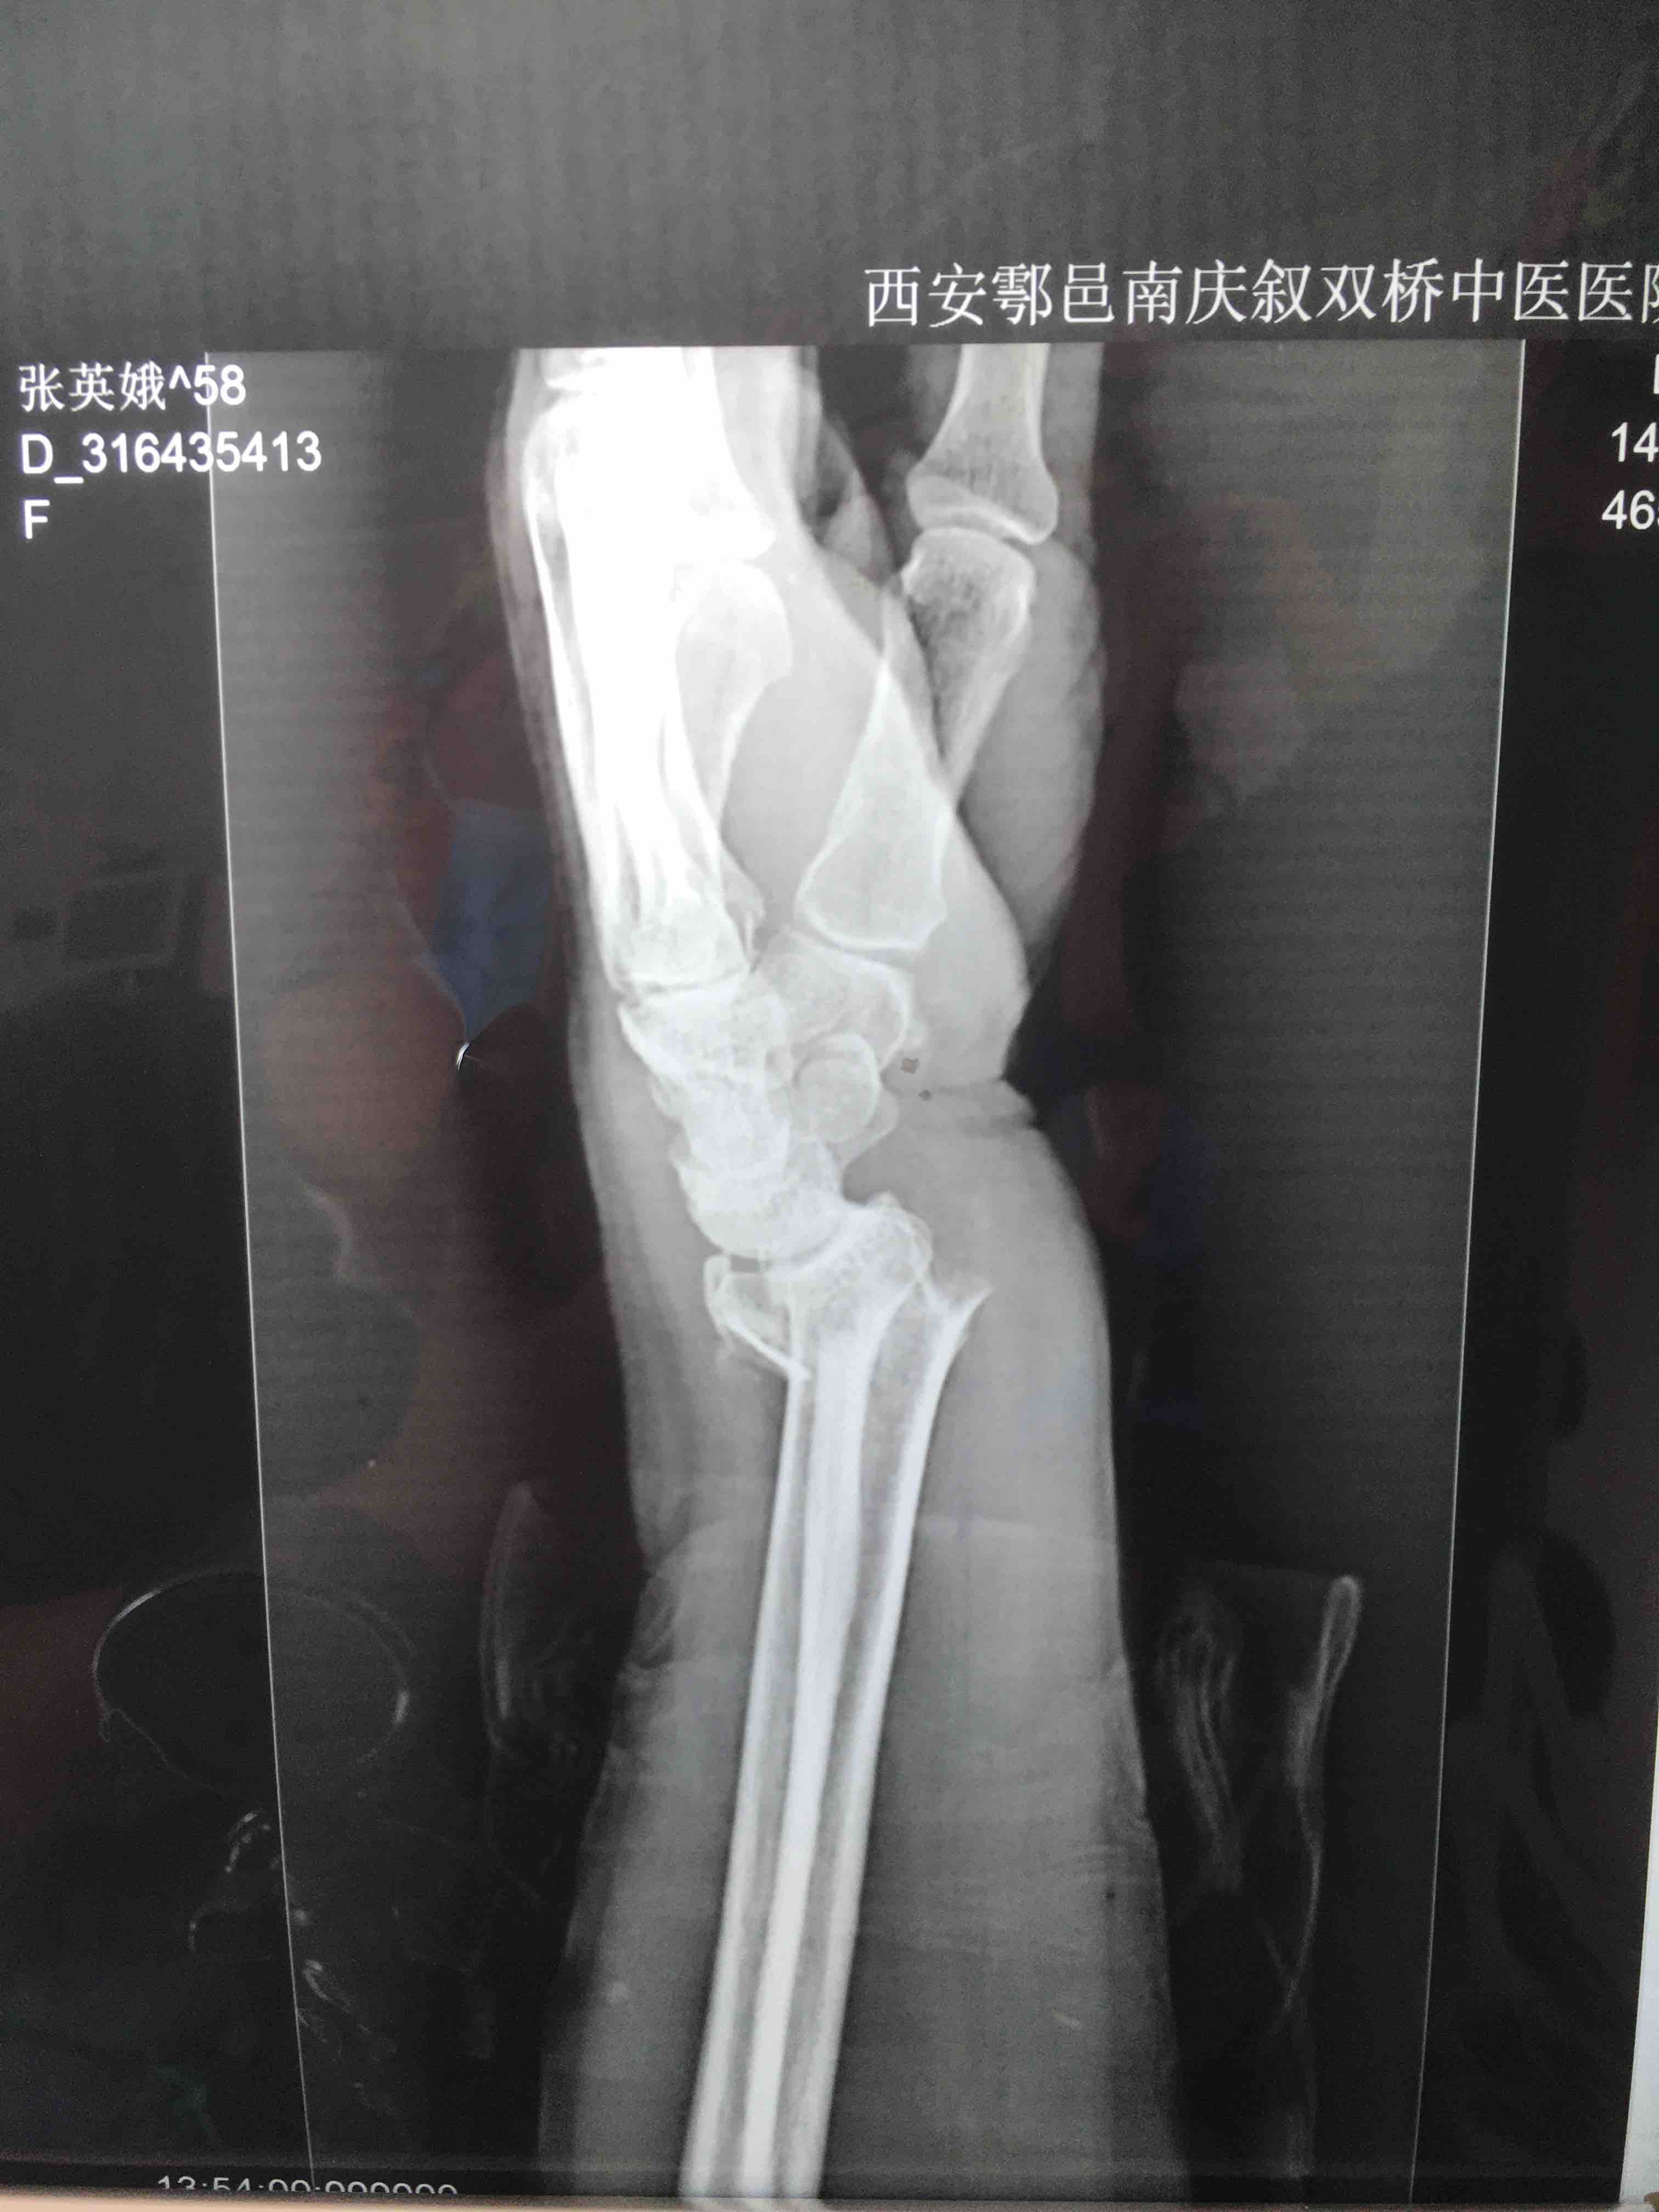

生命体征平稳,心肺复未见异常。左腕部肿胀明显,局部皮色皮温正常,畸形,压痛及纵向叩击痛阳性,腕关节活动受限,感觉血运正常。

诊断左colles骨折

在臂丛下行切复内固定术,术后抗炎消肿等处理。